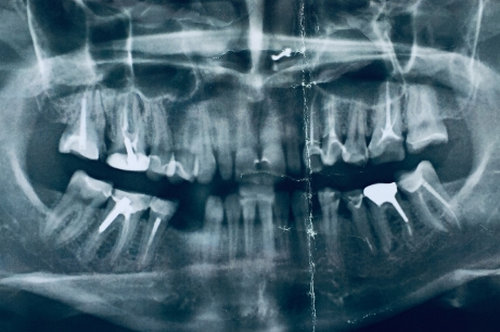

Если при просмотре рентген-снимка пломбировка канала смотрится как нормальная, изменений на верхушке корня нет, то перепломбировывать не надо. Любое вмешательство увеличивает риски, проще говоря, можно сделать хуже.

Другая ситуация, если на снимке выявлены пустоты, не до конца запломбированные каналы, есть разрежения, изменения на верхушке корня, либо зуб ранее побаливал при надавливании, накусывании, слегда поднывал, например при изменении погоды и т.д. В таких случаях лучше зуб перелечить, чтобы избежать проблем с будущей коронкой.